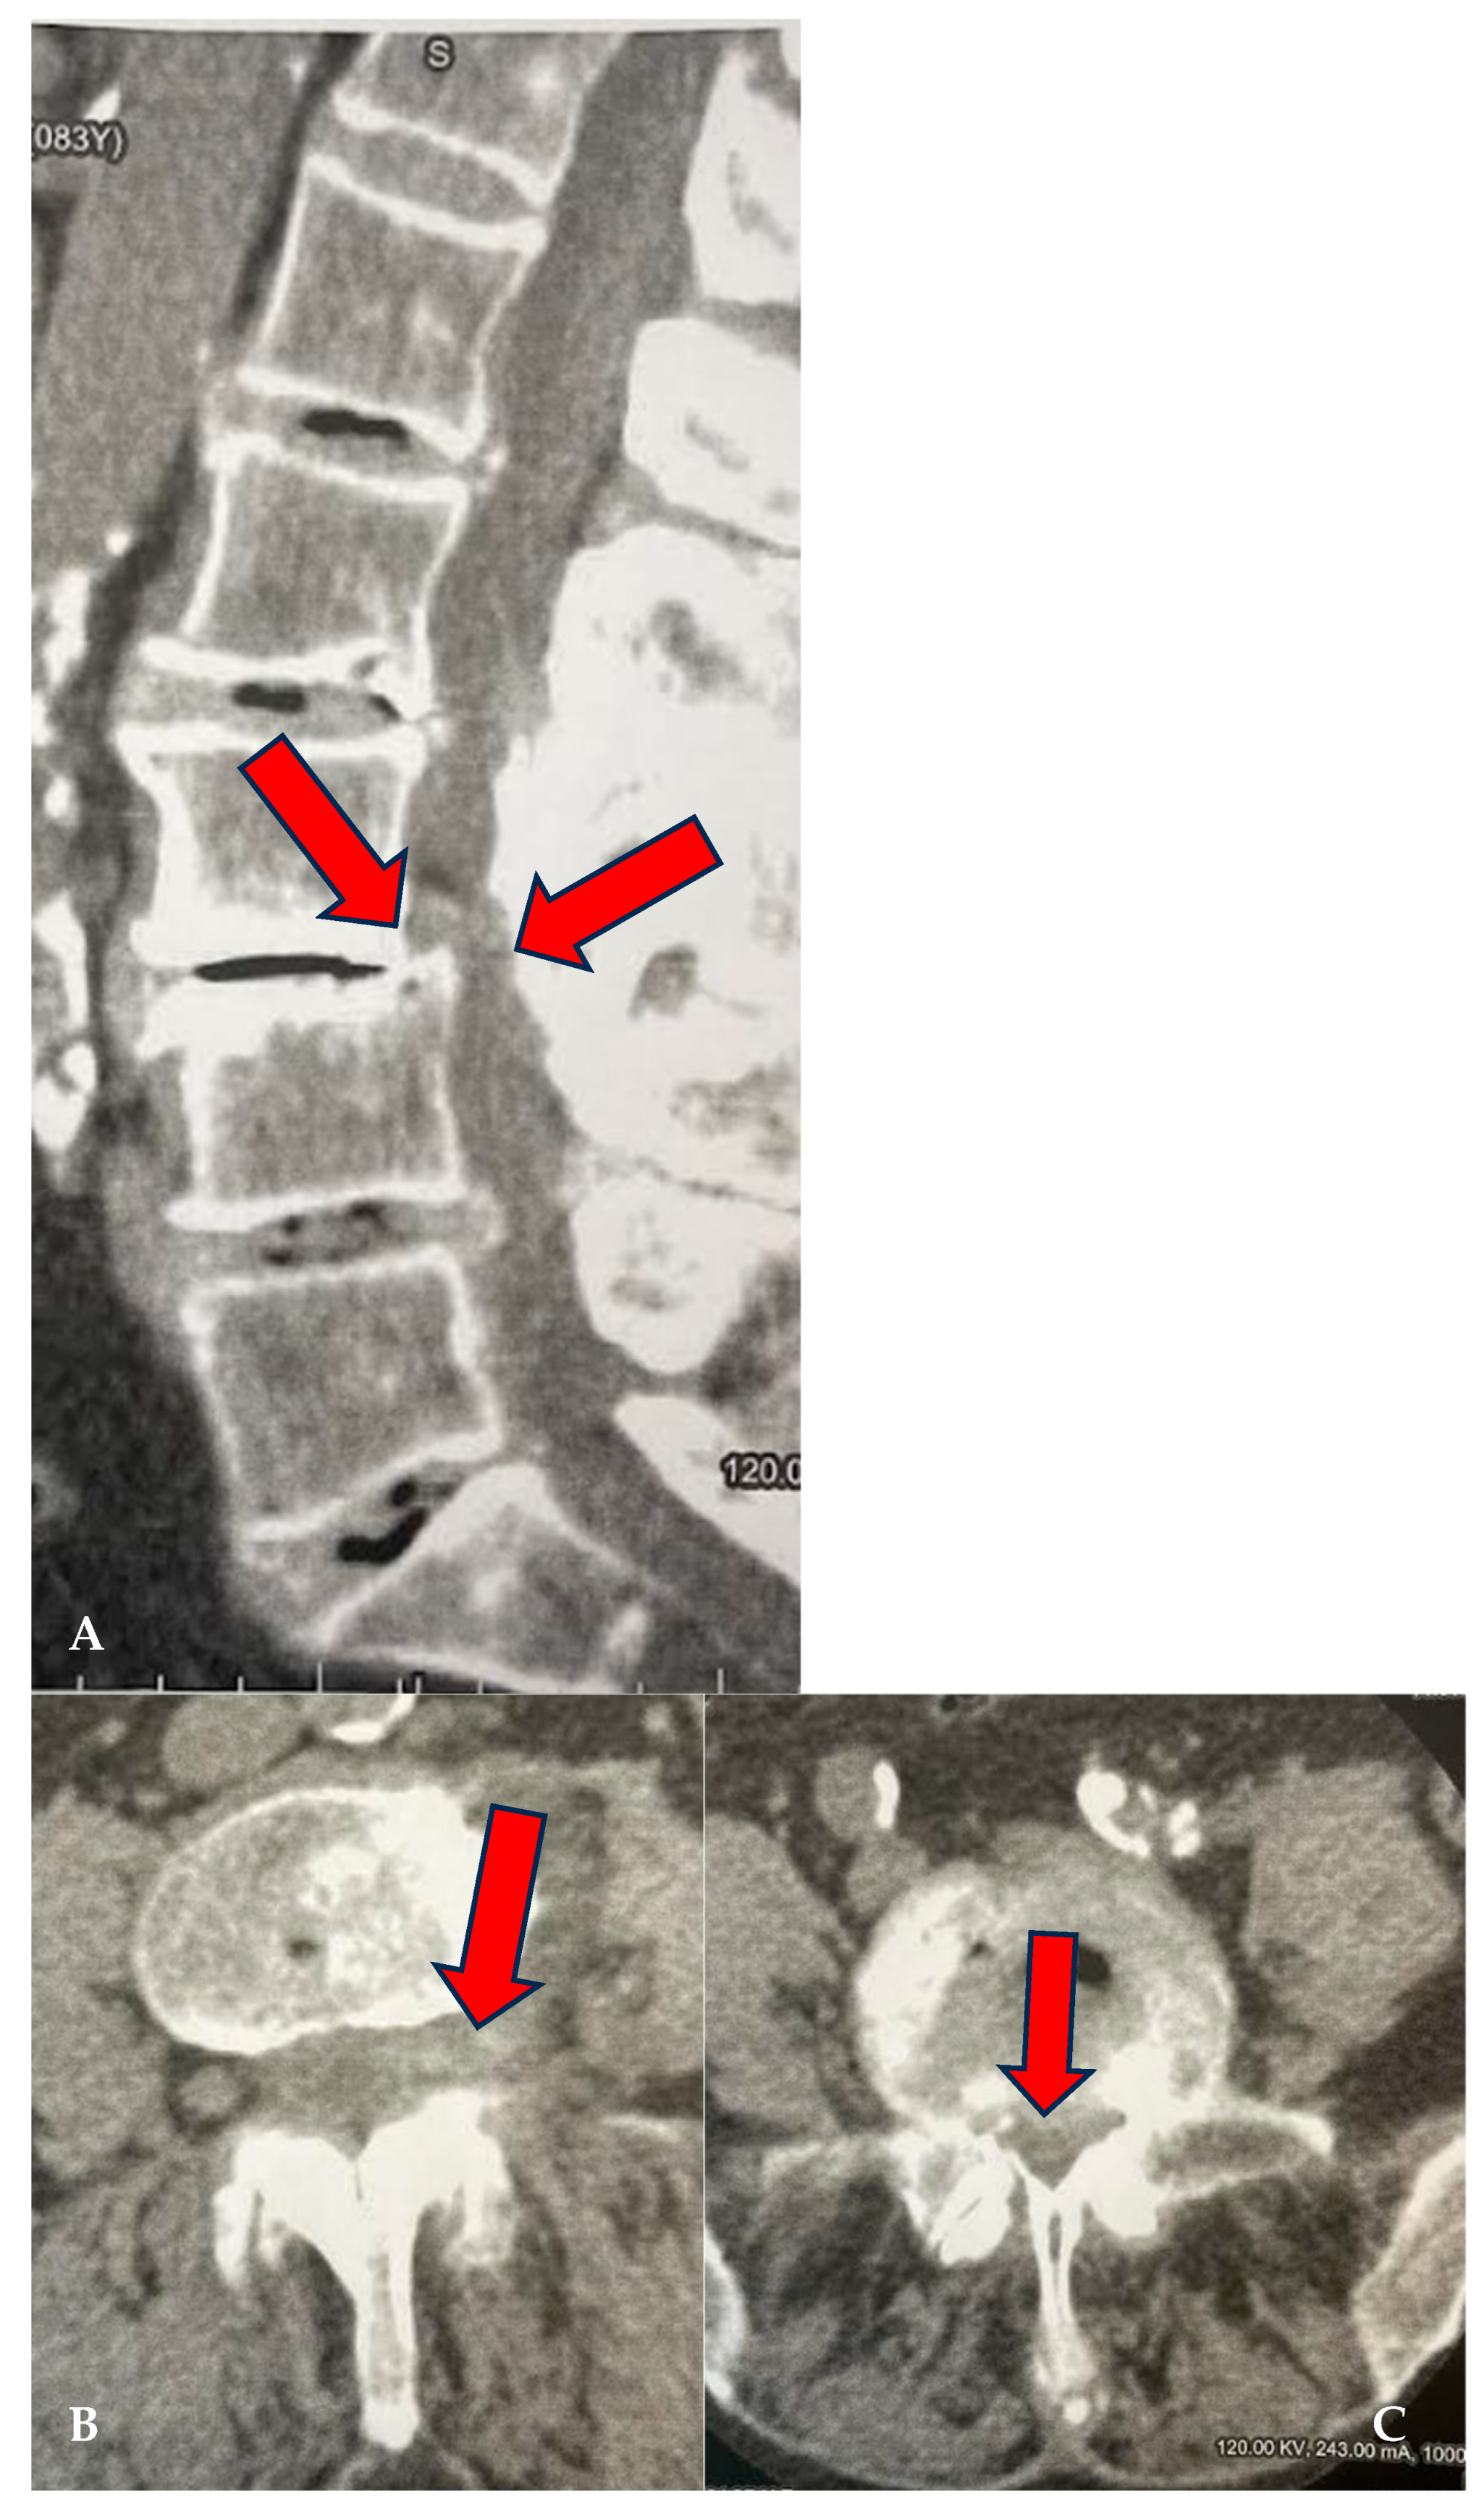

Figure 2.

(A–C): CL of 88-year-old female treated at multiple levels (L3–L4 and L4–L5). At L3–L4, segmental canal stenosis related to pseudospondylolisthesis (A) (red arrows), concomitant intradiscal and foraminal left disc herniation at L3–L4 (arrow) (B), and circumferential disc protrusion at L4–L5 (red arrow) (C).